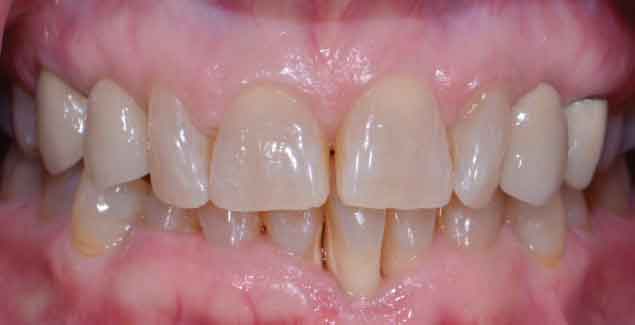

Return to "Modern Applications for The Cantilever Fixed Partial Denture" partial-denture-1 Next Previous